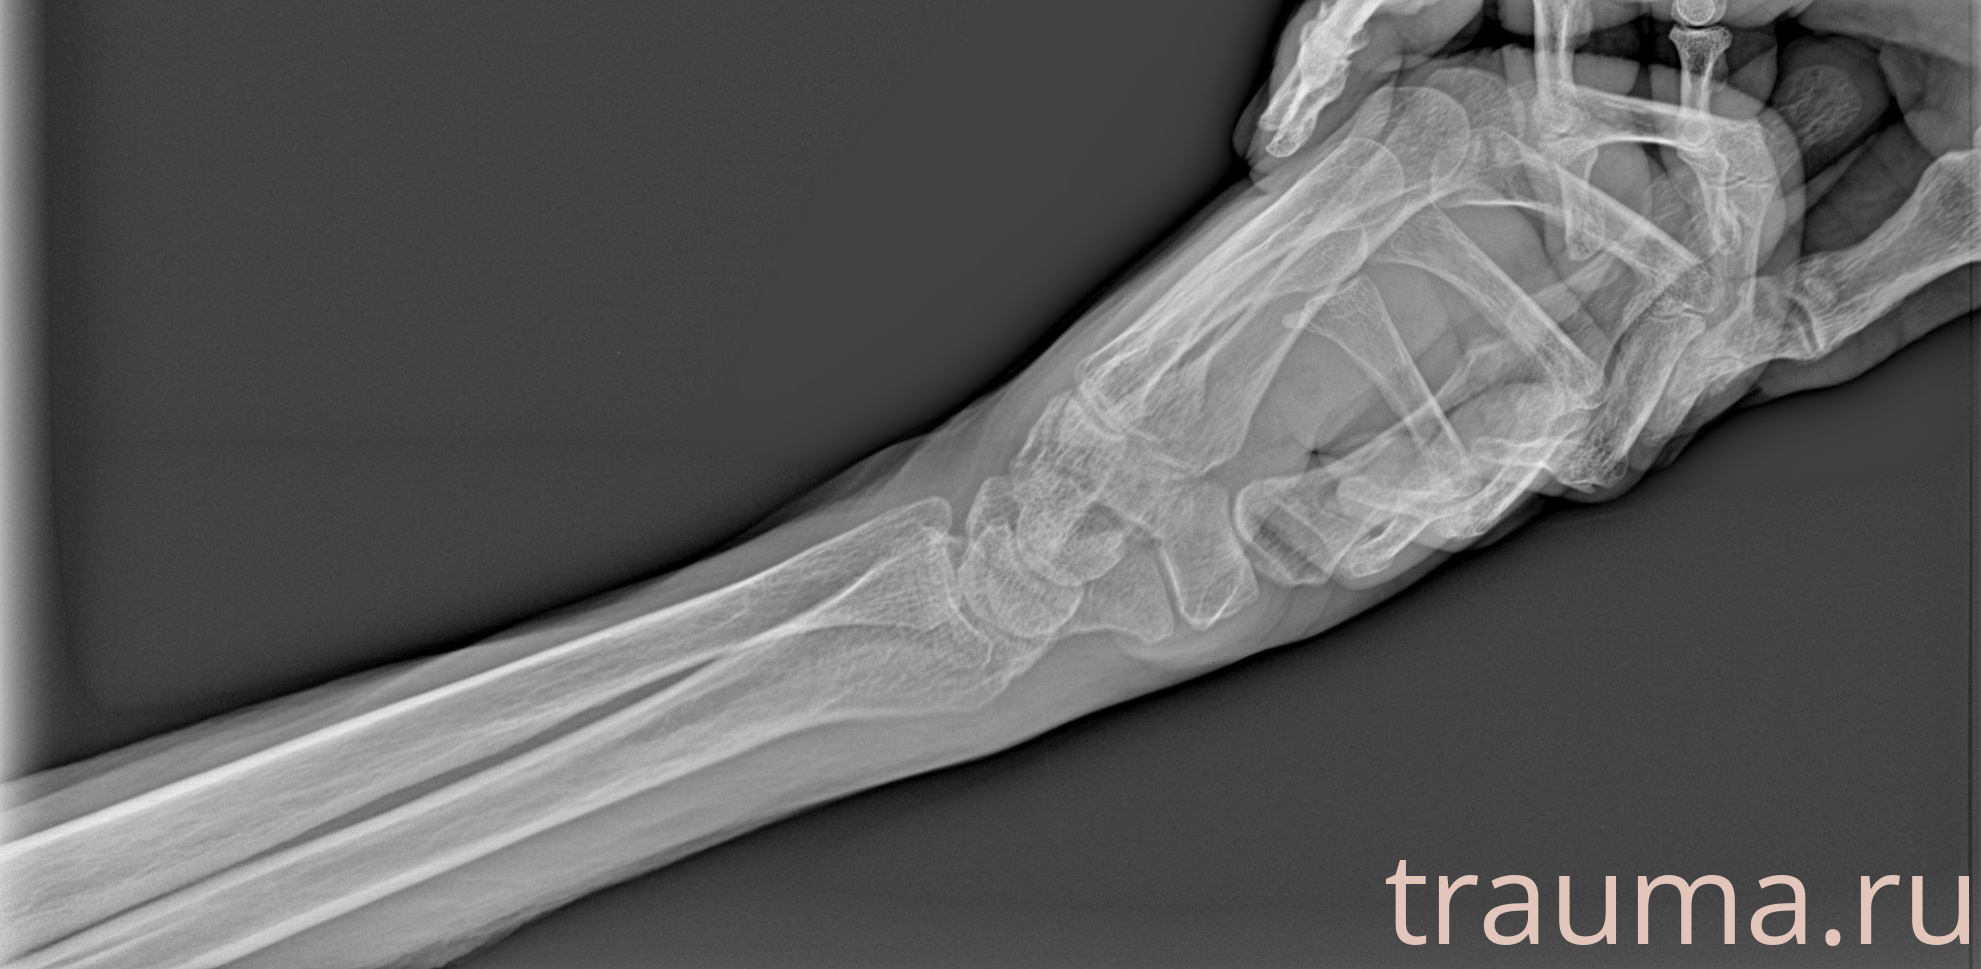

Рентген на дому: по вашему адресу приезжает врач-рентгенолог, травматолог-ортопед с мобильным рентгеновским аппаратом, проводит диагностику травмы или заболевания, делает необходимые рентгенограммы, дает рекомендации по дальнейшему лечению. Получить качественные снимки в домашних условиях возможно благодаря уникальной методике, разработанной МосРентген Центром для института  Склифосовского